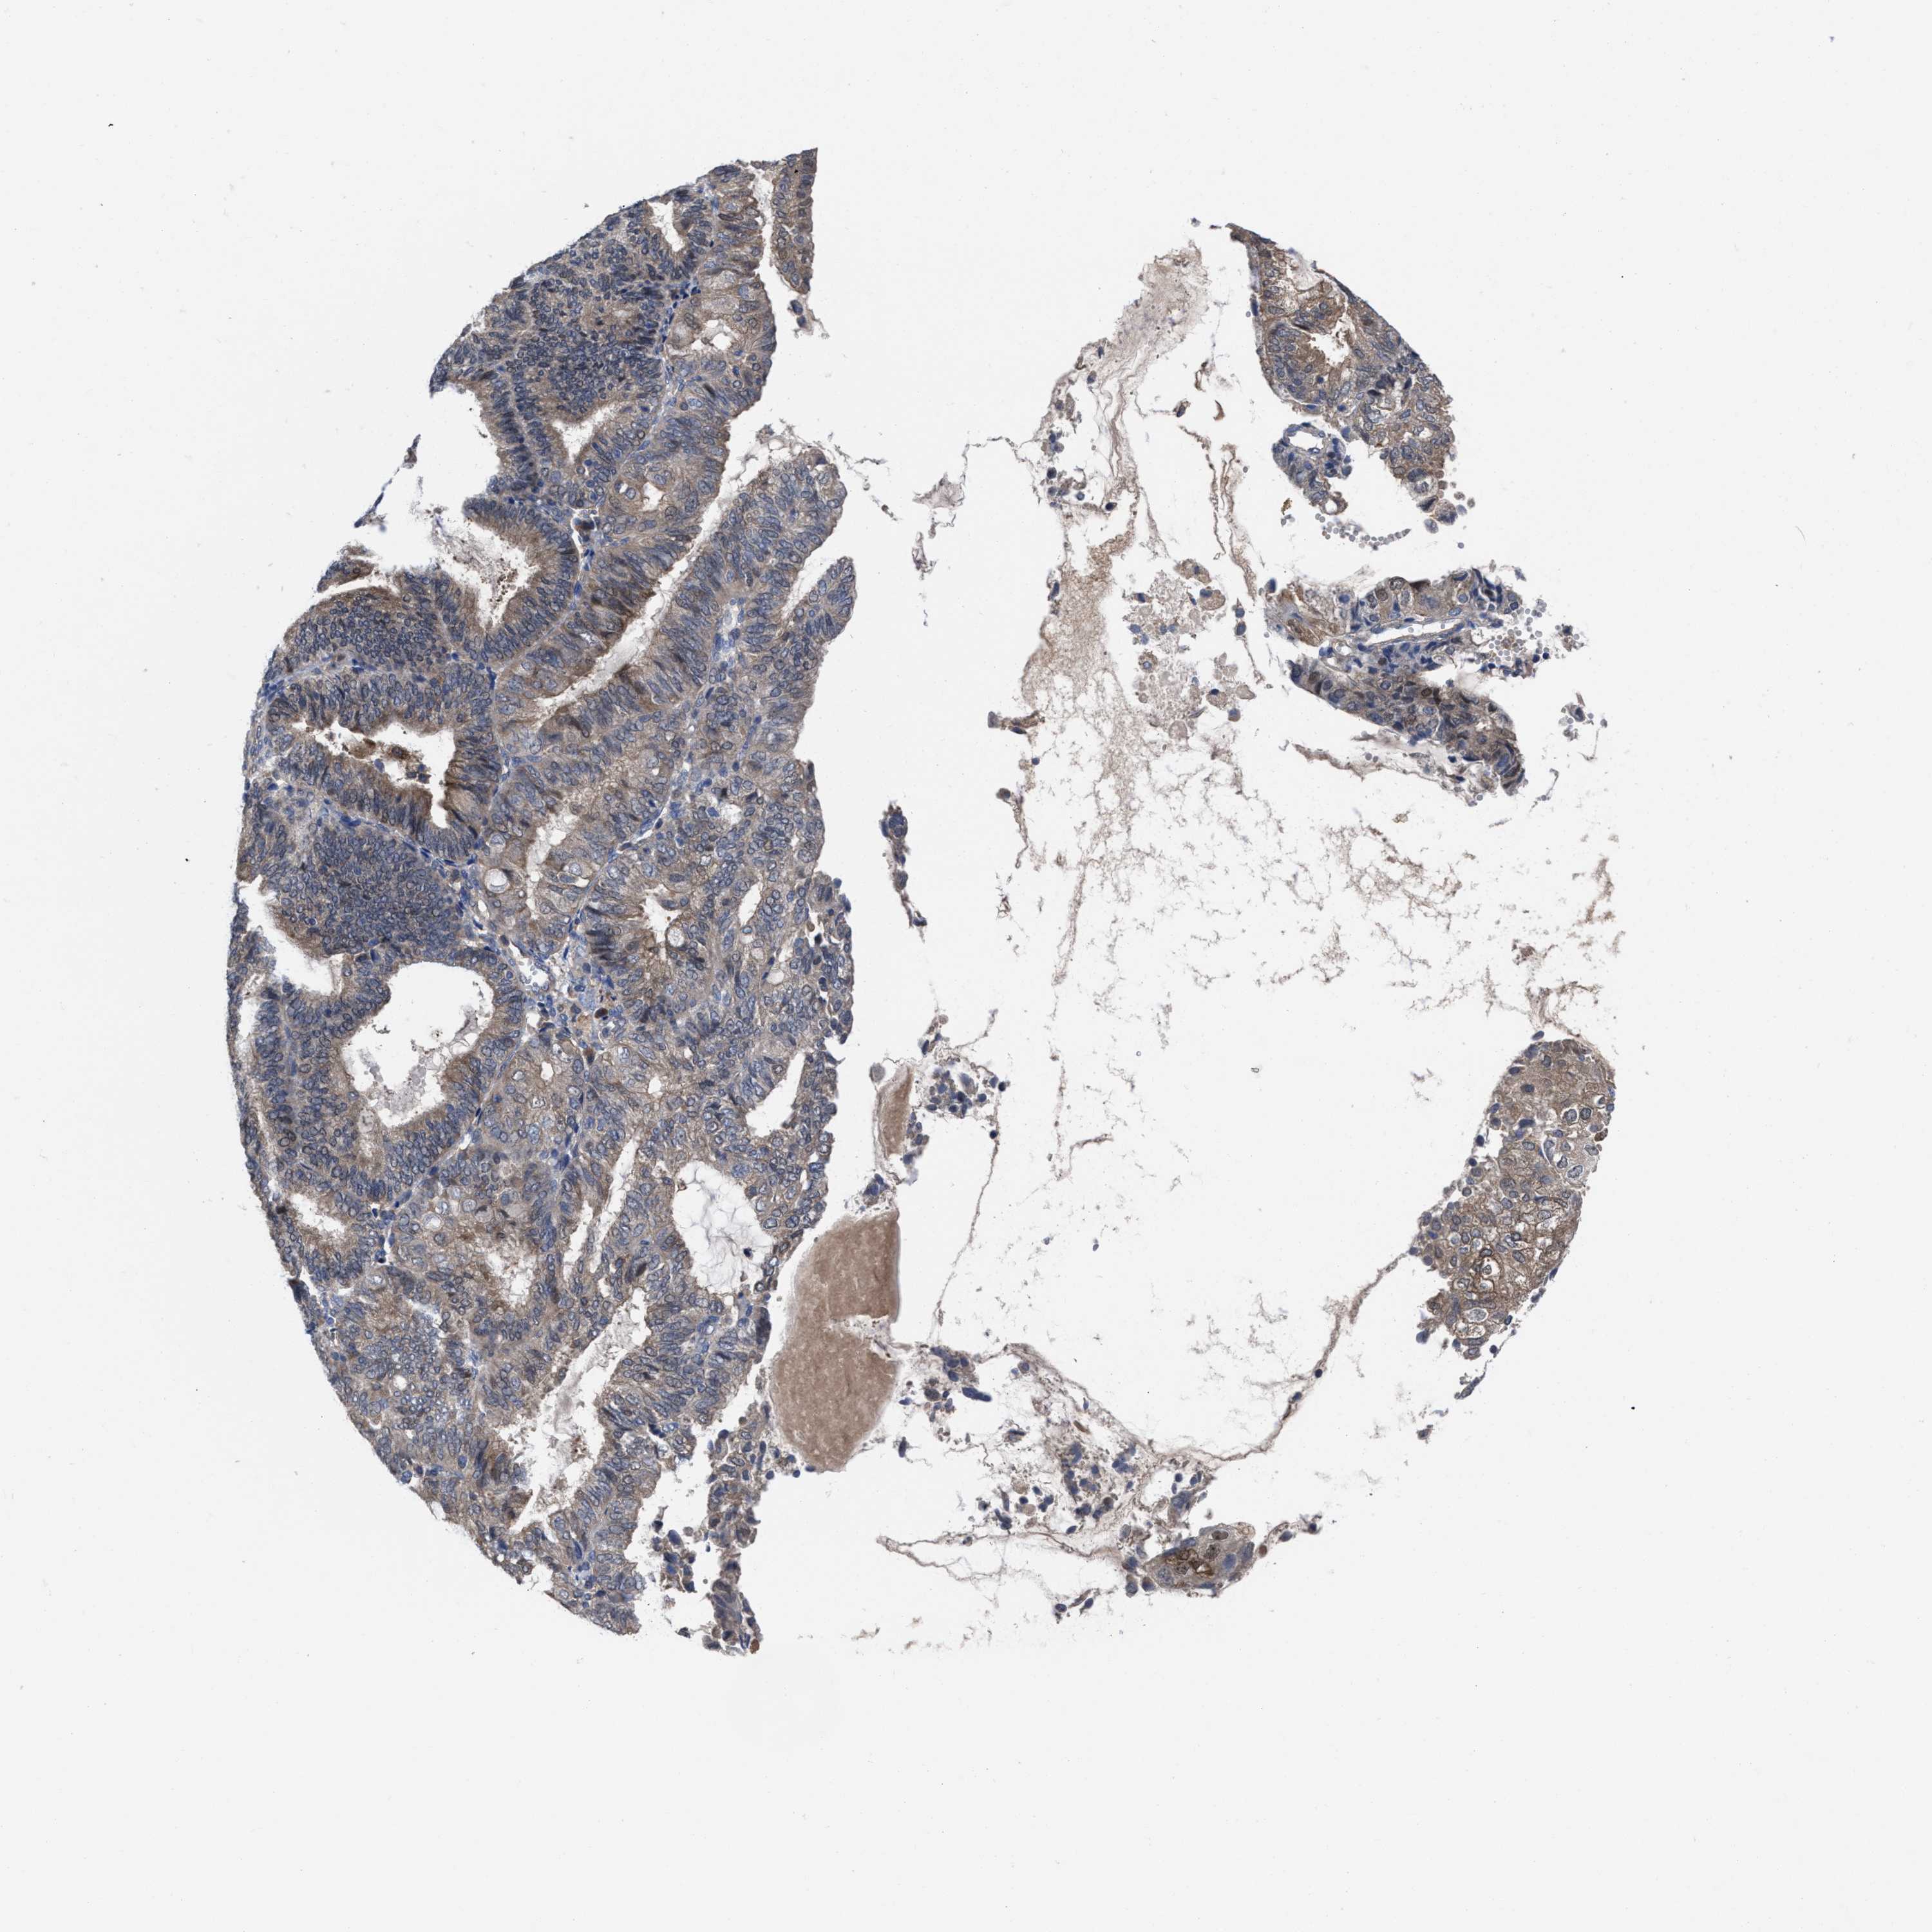

ENDOMETRIAL CANCER - Protein expressioni

A mouse-over function shows sample information and annotation data. Click on an image to view it in a full screen mode. Samples can be filtered based on level of antibody staining by selecting one or several of the following categories: high, medium, low and not detected. The assay and annotation is described here.

Note that samples used for immunohistochemistry by the Human Protein Atlas do not correspond to samples in the TCGA dataset.

Antibody stainingi

Antibody staining in the annotated cell types in the current human tissue is reported as not detected, low, medium, or high, based on conventional immunohistochemistry profiling in selected tissues. This score is based on the combination of the staining intensity and fraction of stained cells.

Each image is clickable and will lead to virtual microscopy that enables deeper exploration of all samples and also displays staining intensity scores, fraction scores and subcellular localization as well as patient and tissue information for each sample.

Antibody HPA022931

Staining

High

Medium

Low

Not detected

Intensity

Strong

Moderate

Weak

Negative

Quantity

>75%

75%-25%

<25%

None

Location

Nuclear

Cytoplasmic/membranous

Cytoplasmic/membranous,nuclear

Adenocarcinoma, NOS

Adenoma, NOS